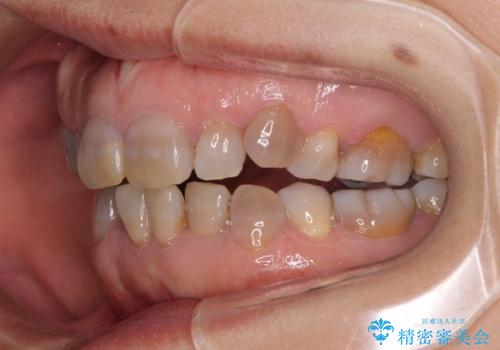

- 小さいころからの歯の変色と矯正治療の後戻りを気にして来院された患者様です。

気になる変色歯を仮歯に変え、その後歯列不正を矯正治療で改善し、最後にオールセラミッククラウンにて補綴治療することとしました。

数十年に及んだ歯の変色が改善されたため、大変満足していただきました。